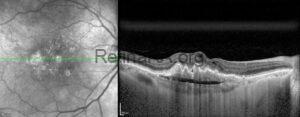

Chronic Central Serous Chorioretinopathy

A 34-year-old male presented with decreased vision in the right eye. Symptoms began 2 years [...]